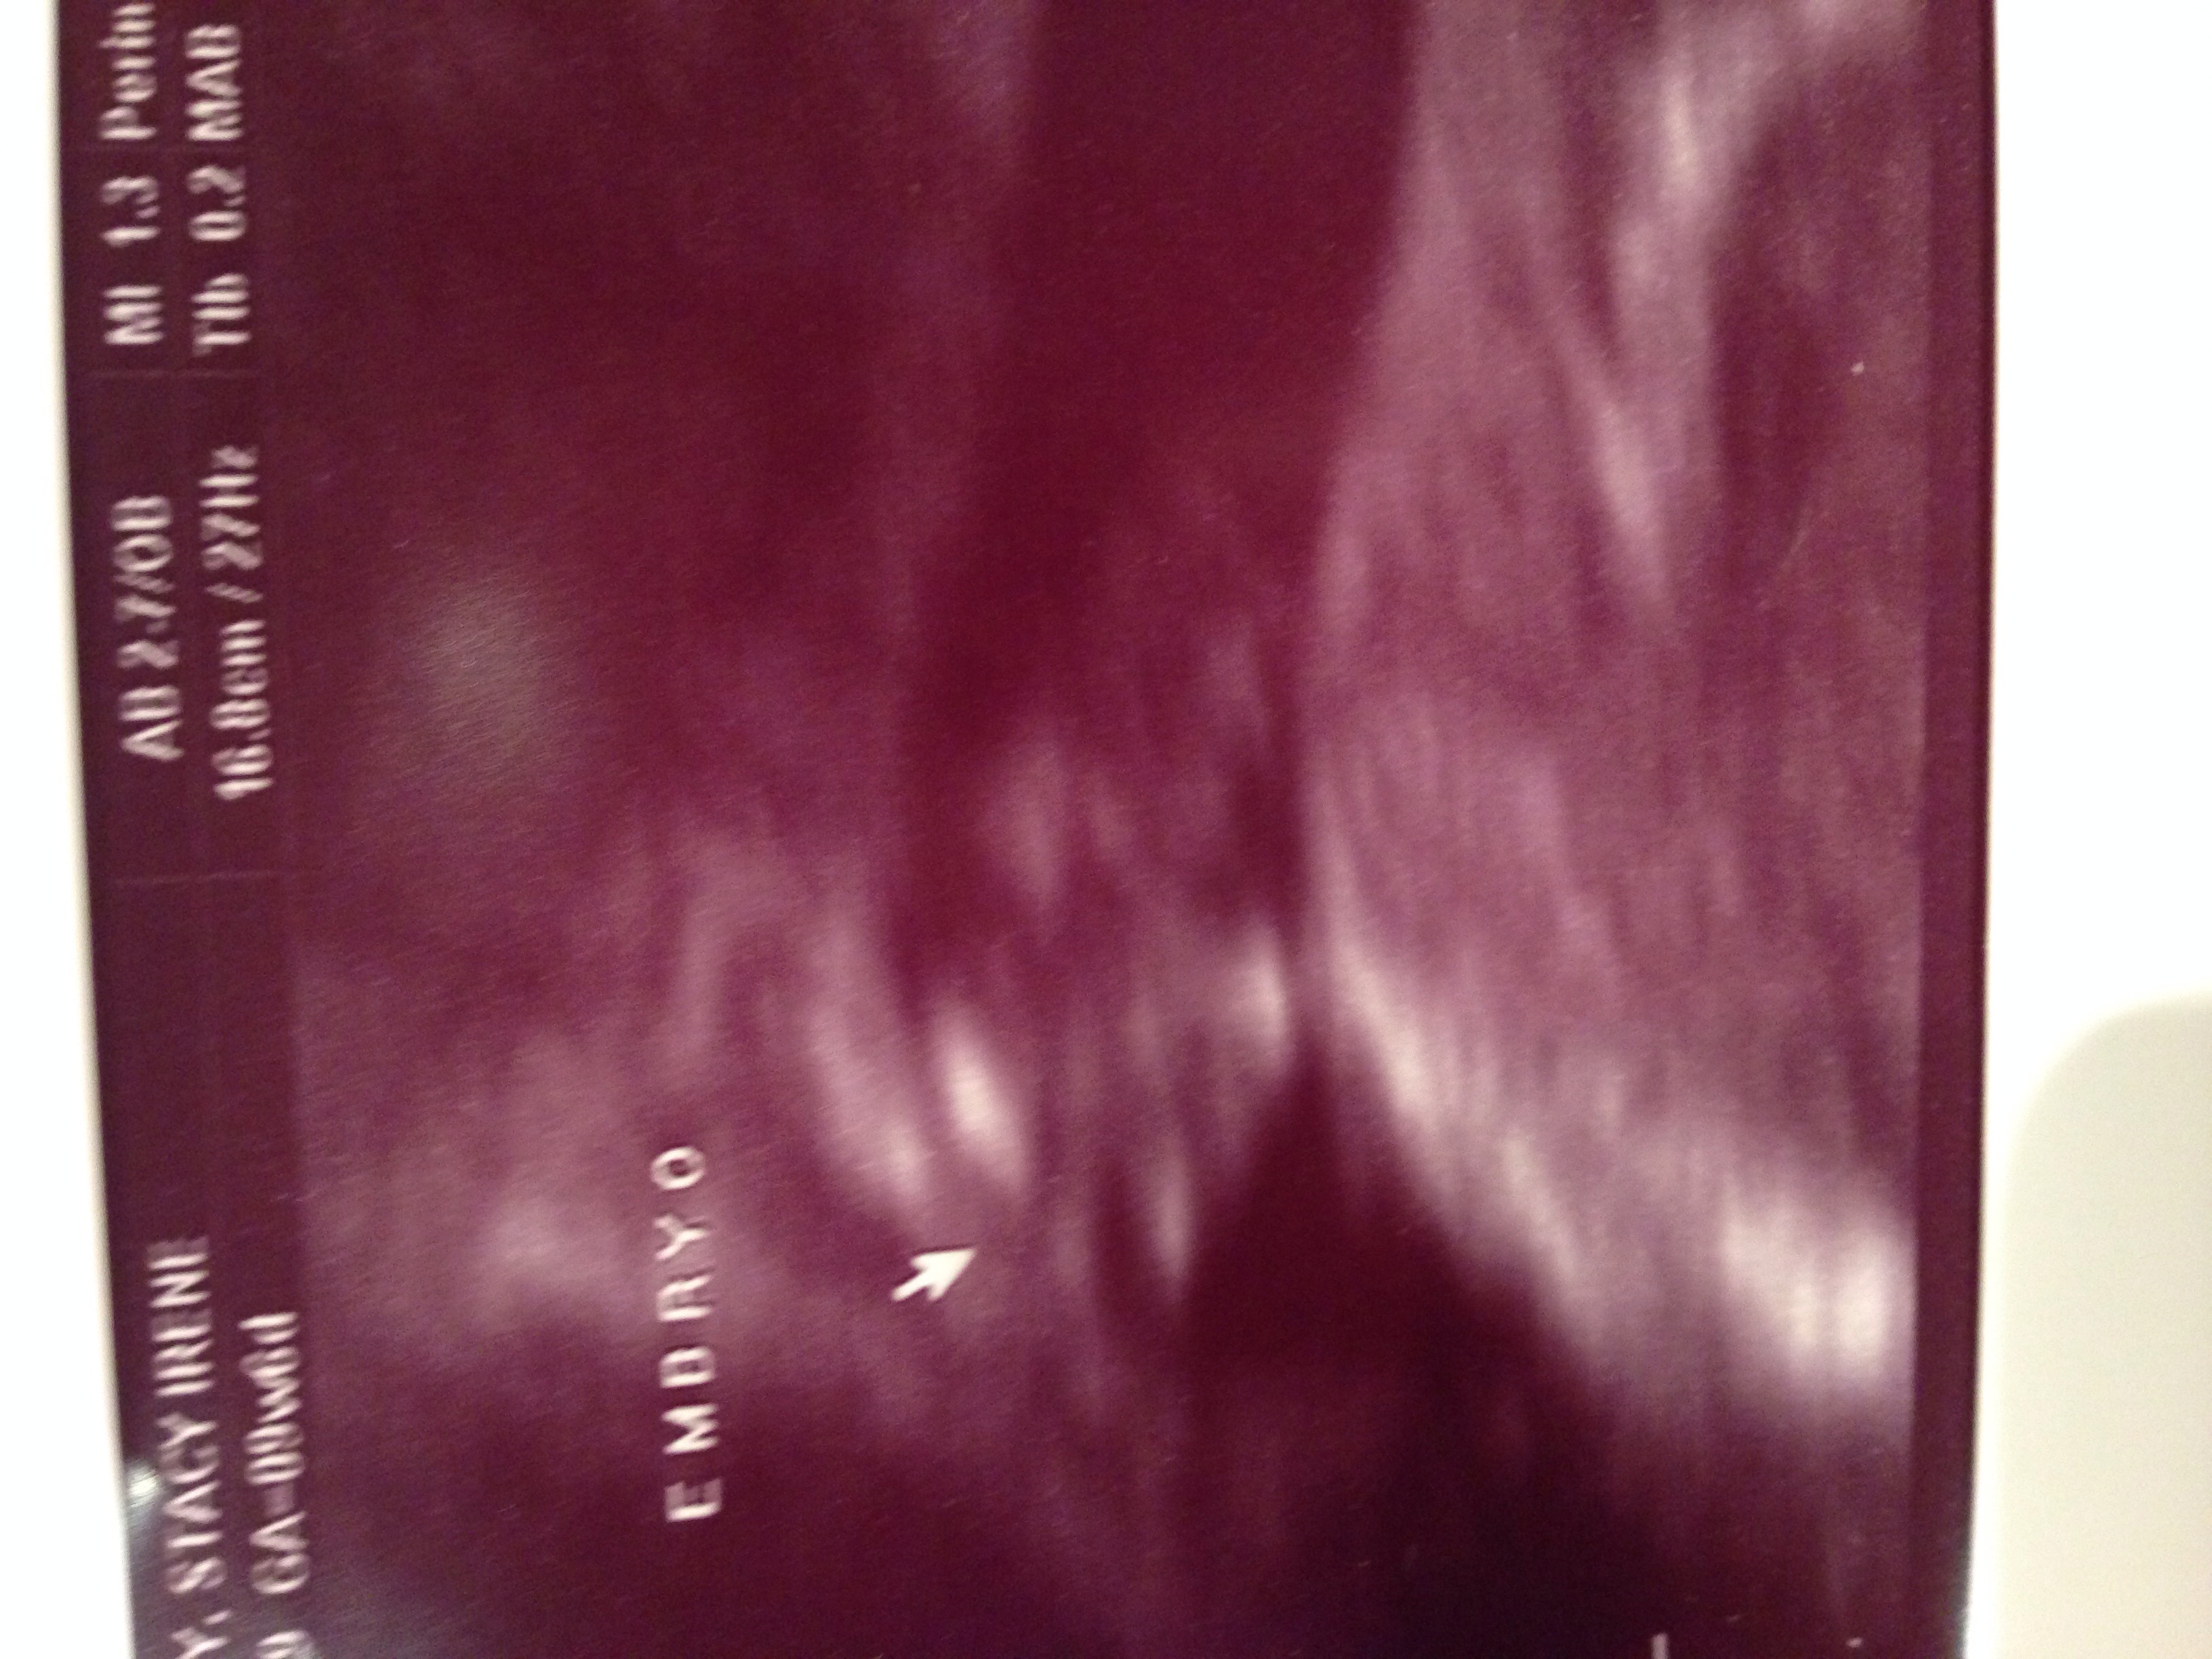

Finally had our first u/s today and I can't even describe how happy I am to see our little embryo! Got a little nervous when they said the baby was measuring smaller but the due date was only pushed back a week. Heart rate was 167; my husband and I both got teary-eyed when we saw that little flicker and heard the heartbeat. Our official due date is June 22nd!!!